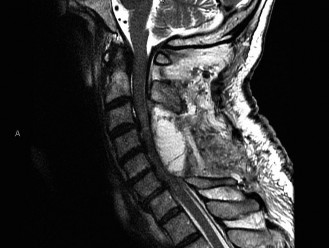

Recognize surgical and nonsurgical indications for a thoracic lymphoma? Definitively manage a thoracic lymphoma? CASE 13 A 23-year-old man was involved in a high-speed motor vehicle accident. On presentation to the trauma bay, his chief complaint was neck pain. Physical examination demonstrated that he was neurologically intact. Images of the cervical spine are shown in Figure 1–19A–B. Full workup demonstrated no other injuries.

Figure 1–19 A–B

The correct answer is (B). The imaging clearly demonstrates a Hangman’s fracture, also known as a C2 traumatic spondylolisthesis. The hallmark of this injury is a fracture through the pars interarticularis of C2, which effectively dissociates the anterior elements from the posterior arch and facet joints. A Jefferson fracture refers to C1 ring fractures that can have varying degrees of lateral displacement. There is no evidence of vertebral body comminution with posterior vertebral body involvement, which would be characteristic of a burst fracture. While some Hangman’s fractures can be associated with facet dislocation, there is no evidence of this on the imaging.

The correct answer is (B). Type I fractures have minimal horizontal displacement, no angulation, and the C2–3 disc remains intact. Type II fractures are both displaced and angulated, presumably hinging around the anterior longitudinal ligament. Importantly, these fractures reduce with longitudinal traction. Type IIA fractures have minimal horizontal displacement but are significantly angulated. It is presumed that the anterior fragment rotates in place, most likely disrupting the anterior longitudinal ligament. These injuries are worsened by traction and reduced with axial compression. Type III fractures have bilateral C2–3 facet dislocations.

The correct answer is (B). While type I fractures can be treated immediately in a hard collar, type II fractures are best treated initially with traction to achieve fracture reduction. After a short period of traction, the patient should be placed in a halo vest to allow mobilization. As indicated above, type IIA fractures should not be placed in traction; patients should be placed in a halo vest with some axial compression applied. Type III fractures require surgical reduction of the facet dislocation and internal stabilization. Objectives: Did you learn...? Identify a Hangman’s fracture based on imaging? Understand the classification of Hangman’s fractures?